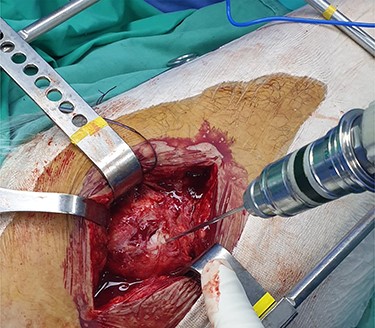

The patient is placed in lateral decubitus position. There is no need of a traction table and fluoroscopy in order to identify the intramedullary canal and the nail inserted. Palpating the prominence of the greater trochanter on the lateral side, an incision is made over it and can be extended distally and proximally. The fasciae latae is carefully incised. The femoral diaphysis and the origin of vastus lateralis are identified. Above the origin of vastus lateralis, k-wires are drilled in order to identify, the anterior and posterior margins of the intramedullary nail in the sagittal plane and mark them and can be left in place (Figs 1 and 2). This is easily performed due to the metal-on-metal effect that is produced during drilling (Fig. 3). Knowing the anterior (point A) and posterior (point P) margins of the intramedullary nail, multiple drillings are performed proximally and perpendicular to the median of the (AP) side of the formed triangle (TAP). The drilling point where no metal-on-metal effect is produced corresponds to the proximal endpoint of the intramedullary nail (point T). Those points form a triangle (TAP) on the lateral side of the femur with the top (T) highlighting the endpoint of the intramedullary nail, and the sides the anterior (A) and posterior (P) margins (Fig. 4). Drilling with k-wires also helps us determine the depth of the nail.

(TAP), is the triangle formed (in red). (T) represents the proximal tip of the intramedullary nail; (A) the anterior margin of the intramedullary nail and (P) the posterior margin of the intramedullary nail.